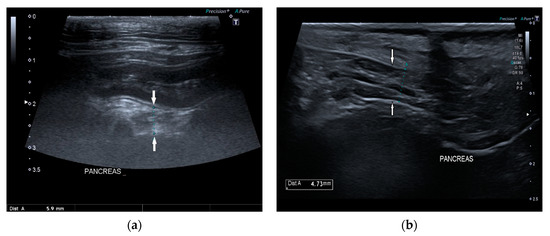

Ultrasonographic Findings of Exocrine Pancreatic Insufficiency in Dogs

by Tina Pelligra, Caterina Puccinelli, Veronica Marchetti and Simonetta Citi

Vet. Sci. 2022, 9(8), 407; https://doi.org/10.3390/vetsci9080407 - 4 Aug 2022

Exocrine pancreatic insufficiency (EPI) is a syndrome characterized by insufficient synthesis of pancreatic enzymes leading to clinical symptoms of malabsorption and maldigestion. There are no studies about ultrasonographic appearance of the pancreas with EPI in dogs. The purpose of this retrospective study was [...] Read more.

Exocrine pancreatic insufficiency (EPI) is a syndrome characterized by insufficient synthesis of pancreatic enzymes leading to clinical symptoms of malabsorption and maldigestion. There are no studies about ultrasonographic appearance of the pancreas with EPI in dogs. The purpose of this retrospective study was to describe ultrasound features of the pancreas during EPI in this species. Dogs with history and clinical signs of maldigestion, serum canine trypsin-like immunoreactivity (cTLI) values <5 µg/L, and abdominal ultrasound exam were included in the study. Size, shape, margin, echogenicity, echostructure, and pancreatic duct appearance of the right pancreatic lobe were valued. Additional sonographic intestinal findings were recorded. Thirty-four dogs were included. The mean pancreatic thickness in our population was significantly lower than the mean reference values of healthy dogs. In 68% of dogs, the pancreas had a normal ultrasound appearance. Ultrasonographic intestinal abnormal findings were identified in 85% of dogs and were suggestive of inflammatory bowel disease. Despite the fact that EPI is a functional diagnosis, ultrasound evaluation should be considered among the useful tests. The finding of a normal but thinned pancreas associated with sonographic intestinal signs of inflammatory bowel disease in dogs with typical history and supportive clinical signs could suggest a diagnosis of EPI. Full article

Show Figures

Figure 1